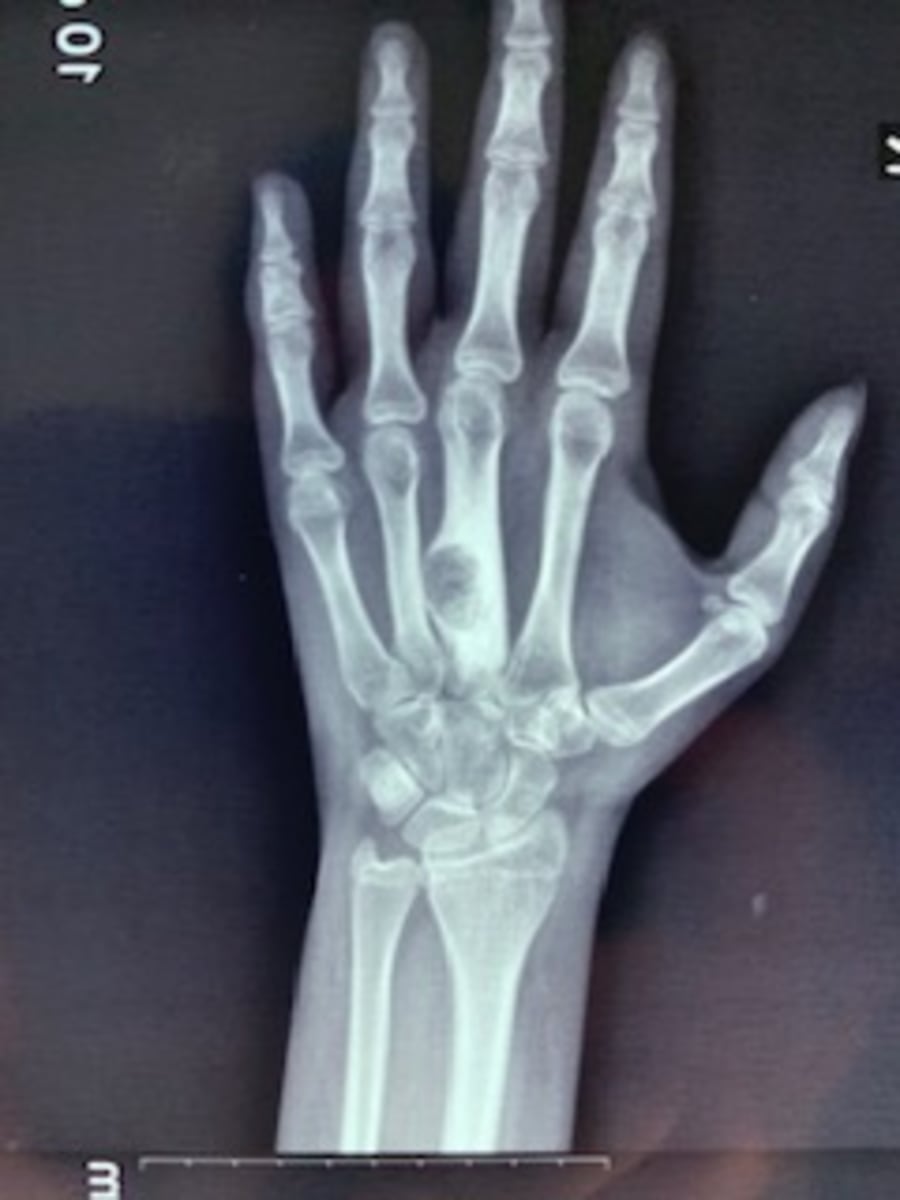

Our week begins by renewing old acquaintances, setting up operating rooms and triaging patients for surgery (Image 1). Patients are sent from the surrounding area, mostly from small villages that do not normally have access to orthopedic care or who cannot afford it. I am responsible for taking care of patients with hand and upper extremity problems. We see quite a variety of conditions including both adult and pediatric patients, congenital differences, fractures, fracture malunions, nerve palsies and extremity tumors. Theses problems are frequently made more challenging due to a significant delay in receiving treatment, initial mismanagement of a problem, and also the lack of resources for obtaining post-operative care such as physical and occupational therapy.

A few examples of the patients and conditions we treated are now presented. Images 2-4 are of an 8 year old boy with symbrachydactyly. He required syndactyly release of the first web space and z-plasty of the small finger. Images 5-6 are of a patient with a severe wrist flexion contracture due to longstanding neuromuscular disorder. Image 6 is an intraoperative photo of his fused wrist. Images 7-8 are of a patient with a benign bone tumor. Images 9-11 demonstrate treatment of a patient with a distal radius fracture. In the US, this would be fairly easily treated with early open reduction and internal fixation. This fracture was made more challenging in that it was eight months old. On rare occasions, we are also able to treat acute fractures.